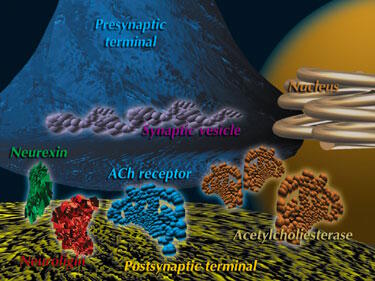

| Les mécanismes d'action de la Galantamine